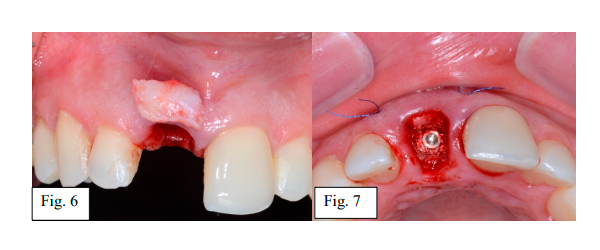

Durante os ajustes e acabamentos do provisório, simultaneamente, foram iniciadas as etapas regenerativas para preservação da morfologia tecidual do osso e dos tecidos moles. Nesta etapa, foi feito preenchimento com substituto ósseo natural bovino aglutinado em colágeno (Extra Graft / Silvestre Lab.), no espaço peri-implantar intra-alveolar, entre o implante e a parede integra do osso vestibular. Em seguida, tunelização na mucosa vestibular ao alvéolo e fixação com suturas (polipropileno 6.0) do enxerto tecido conjuntivo na zona supracristal para aumento de volume dos tecidos moles (Fig. 6 e 7).

Por fim, o provisório foi instalado sobre o implante com morfologia côncava na área submucosa, definindo a zona subcrítica e o contorno da margem mucosa coronária delimitando a zona crítica (Fig. 8 e 9).